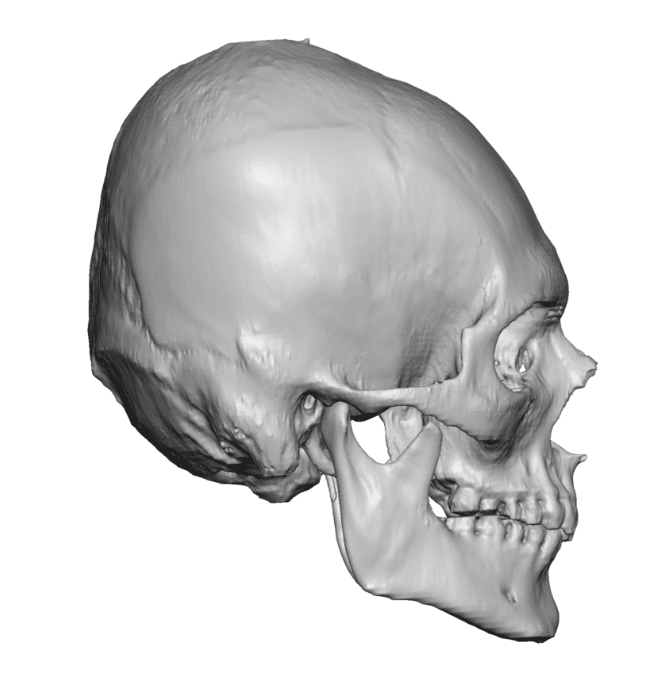

Desire for rounder shape to the top of the head from a congenital parasagittal deficiency skull shape.

Custom skull implant designed to fill in the parasagittal deficiencies.

Desire for rounder shape to the top of the head from a congenital parasagittal deficiency skull shape.

Custom skull implant designed to fill in the parasagittal deficiencies.